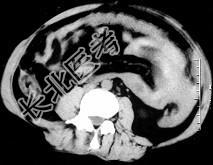

- 单项选择题女,32岁, 因停经46天,突发腹痛1天入院, 后穹隆穿刺抽出不凝血,CT检查如图所示, 下列说法错误的是 ( )

A、在左附件区可见一椭圆形略高密度病灶

B、病灶外缘较光整

C、盆腔内较高密度积液

D、此为宫外孕

E、此为卵巢巧克力囊肿